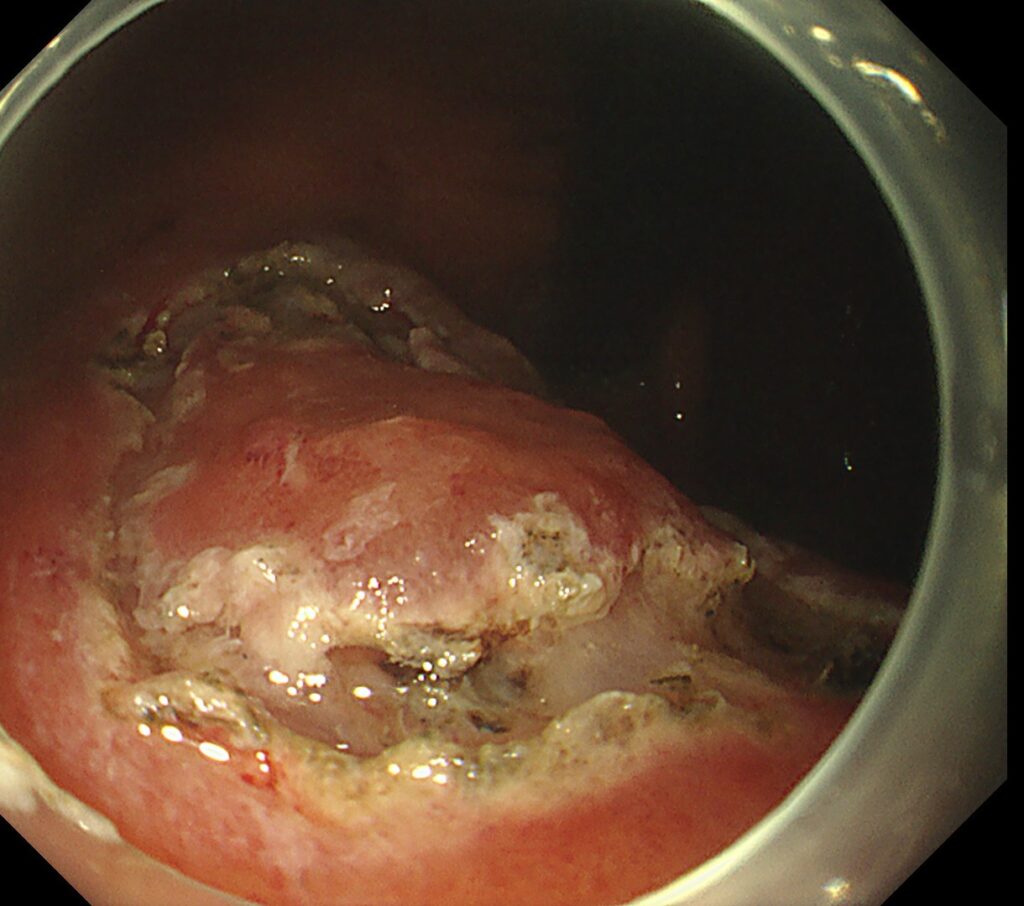

穿通するほどですので、胃は強く変形しており、わかりやすい写真がとれず・・・。

付図のごとく、胃の小彎側に、突如ひだが途絶するほどの潰瘍瘢痕を認めます。

その直上に

易出血性の陥凹性病変を認めます。